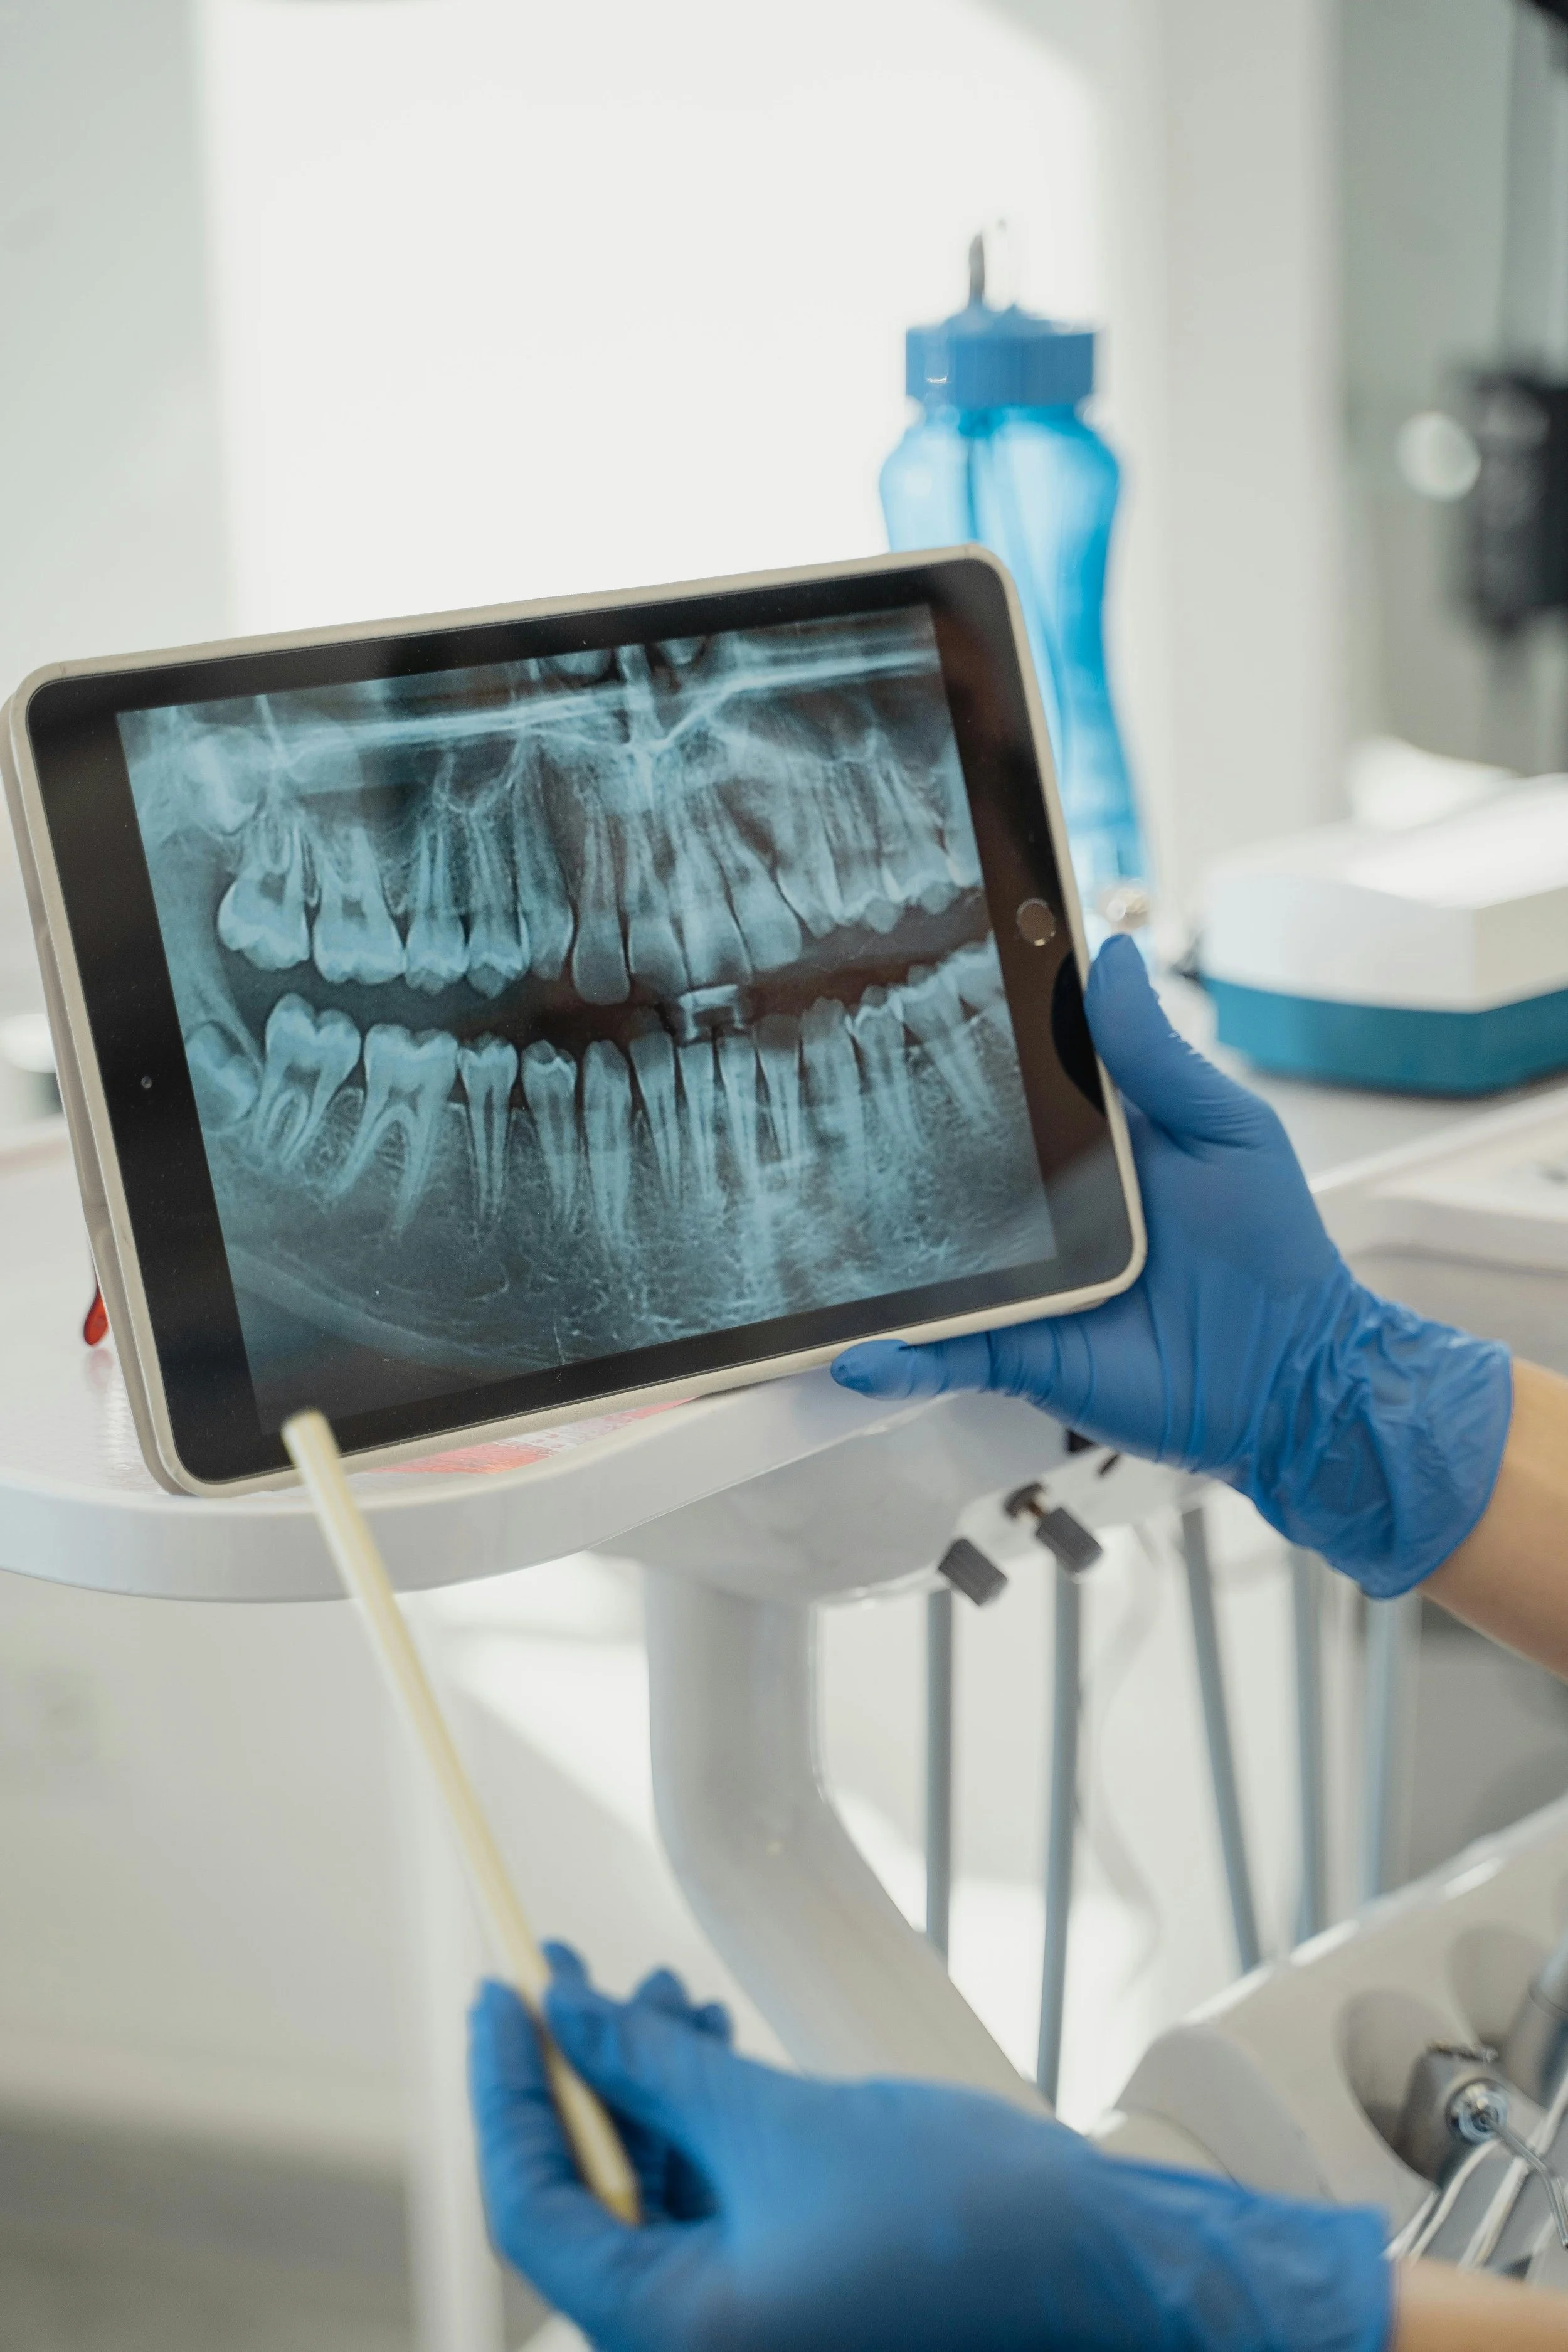

Root Canal Treatment

Root canal treatment is a procedure used to address infection or damage within the pulp (nerve) of a tooth.